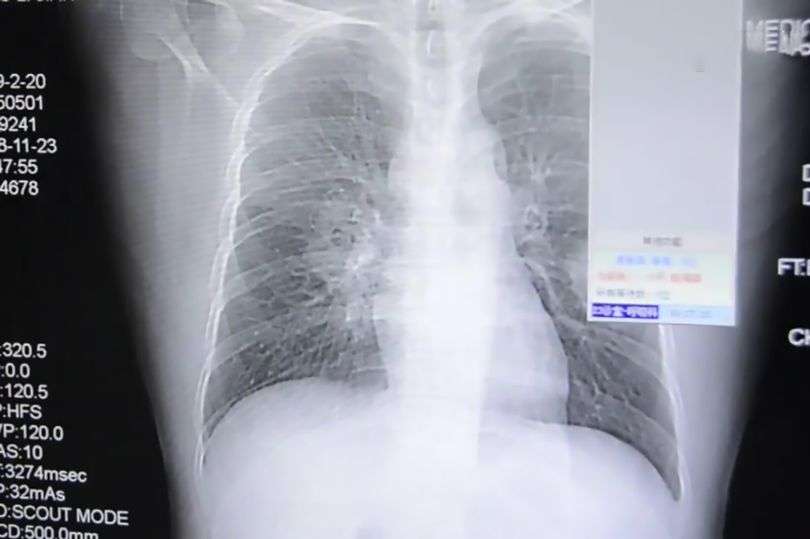

Saat diperiksa dan dilakukan X-ray, barulah terungkap bahwa Peng mengalami infeksi paru-paru yang parah.

Dari pemeriksaan lanjutan terdapat sebuah fakta yang mengagetkan, infeksinya itu ternyata disebabkan oleh bakteri yang biasa di temukan di alas kaki.